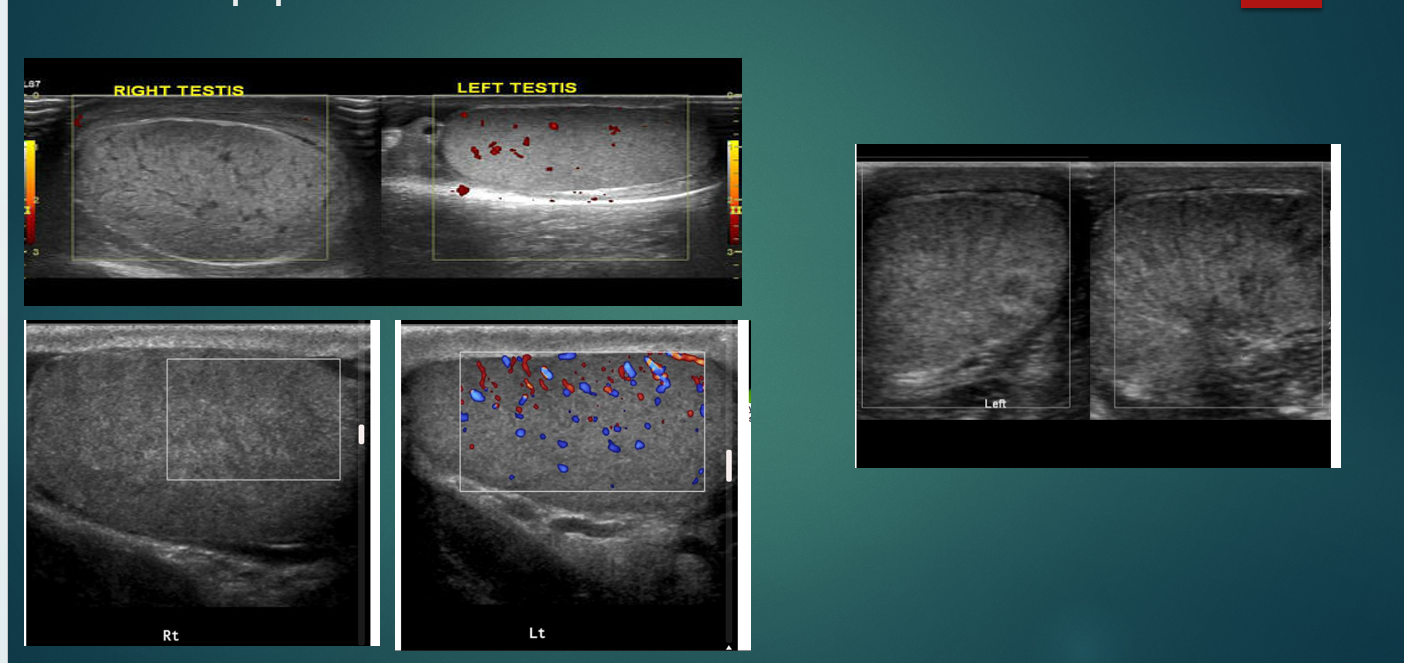

Varicocele

what does the image show

torsion